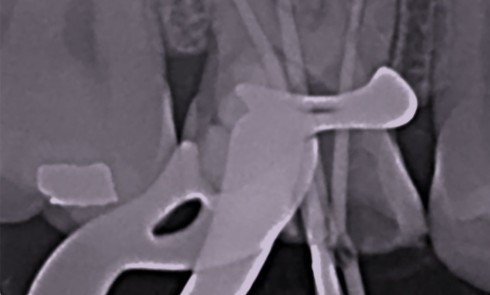

Perforation supra-osseuse (fig. 1) Les perforations supra-crestales sont la plupart du temps iatrogéniques et surviennent lors de la réalisation de la...